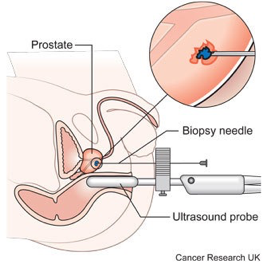

An ultrasound of the urinary tract can help assess the size of a bladder tumor and whether a bladder cancer has spread. Ultrasound is able to differentiate between fluid-filled cysts and solid tumors, however, it cannot determine if a tumor is cancerous. Ultrasound can also be used to guide a biopsy needle to sample a suspected cancer.

What is the biopsy for bladder cancer?

A biopsy is when tiny pieces (called samples) of the abnormal-looking tissue are taken out and tested for cancer cells. If bladder cancer is suspected, a biopsy is needed to be sure of the diagnosis.